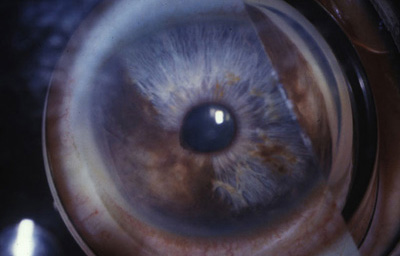

Melanoma sólido nodular del Iris con lente de Gonioscopía

Archivo Fotográfico Dr. Francisco Barraquer.

El circunscrito, es una masa solitaria nodular en el estroma del Iris, con variables grados de pigmentación, con vasos nutricios intrínsecos en el estroma o dentro del ángulo. (31,32,33)

Melanoma sólido nodular del Iris

Archivo Fotográfico Dr. Francisco Barraquer.